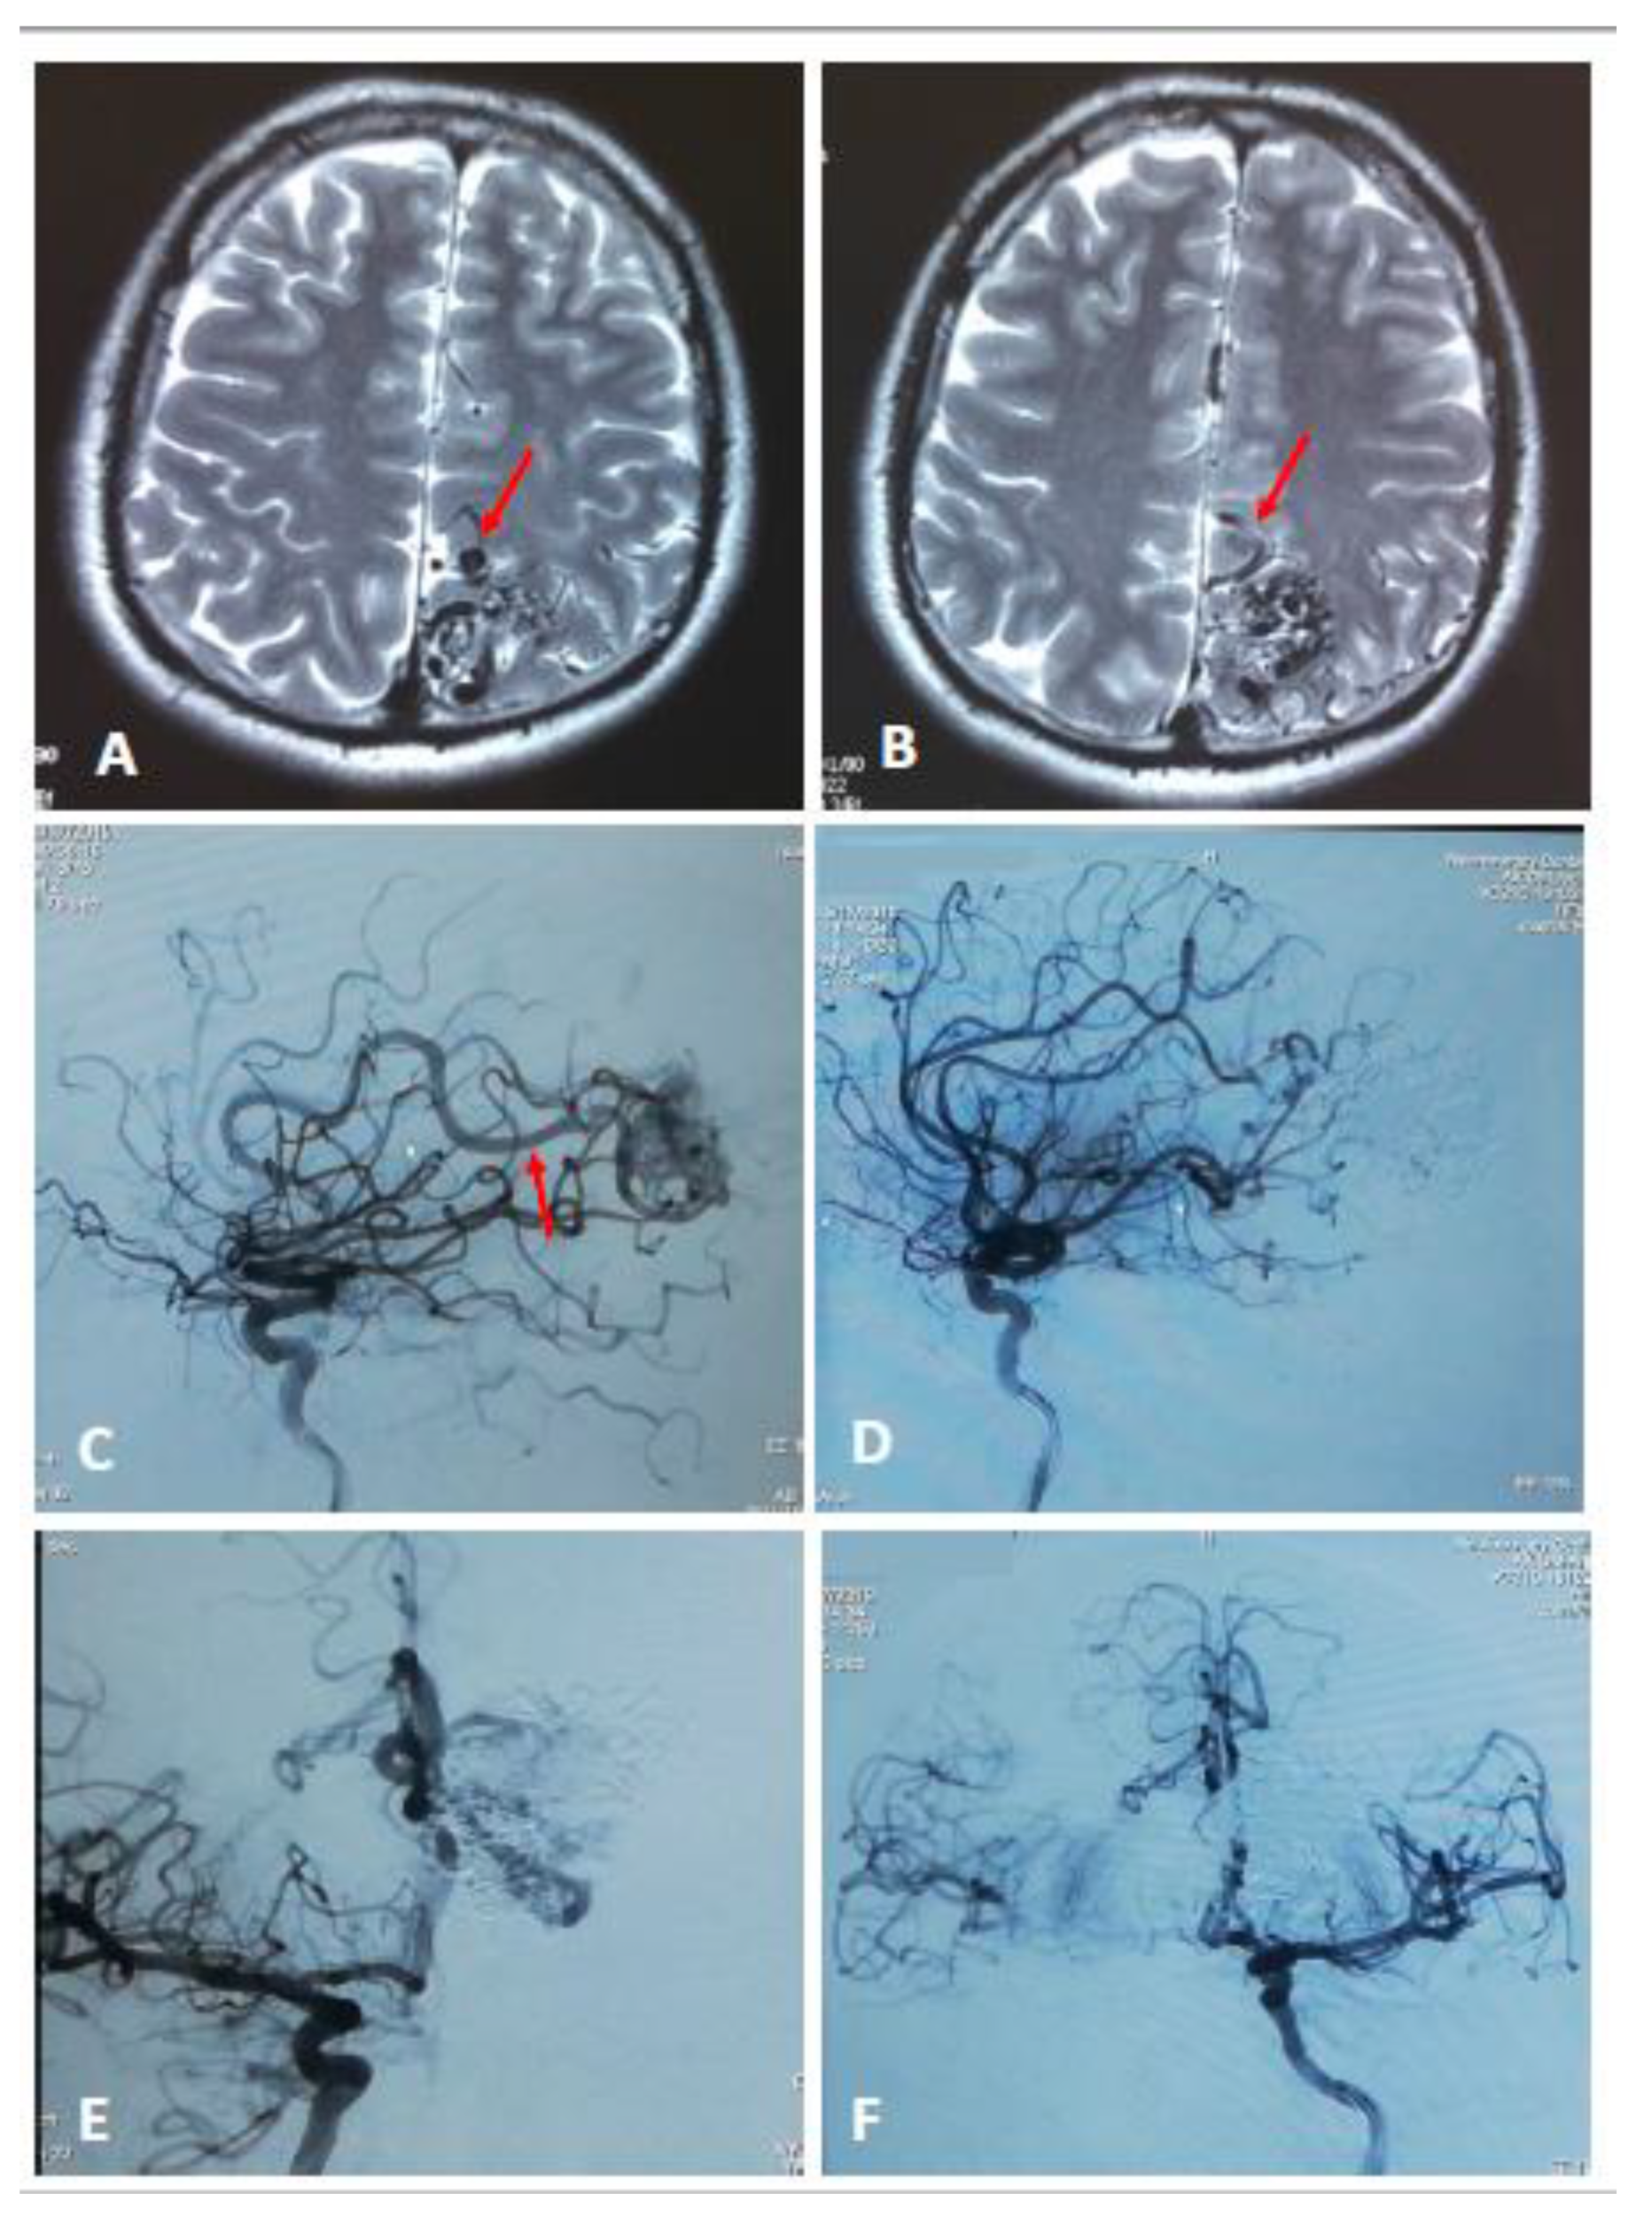

2. Materials and Methods

2.2. Diagnosis of Brain AVMs

2.3. Endovascular Embolization Procedure